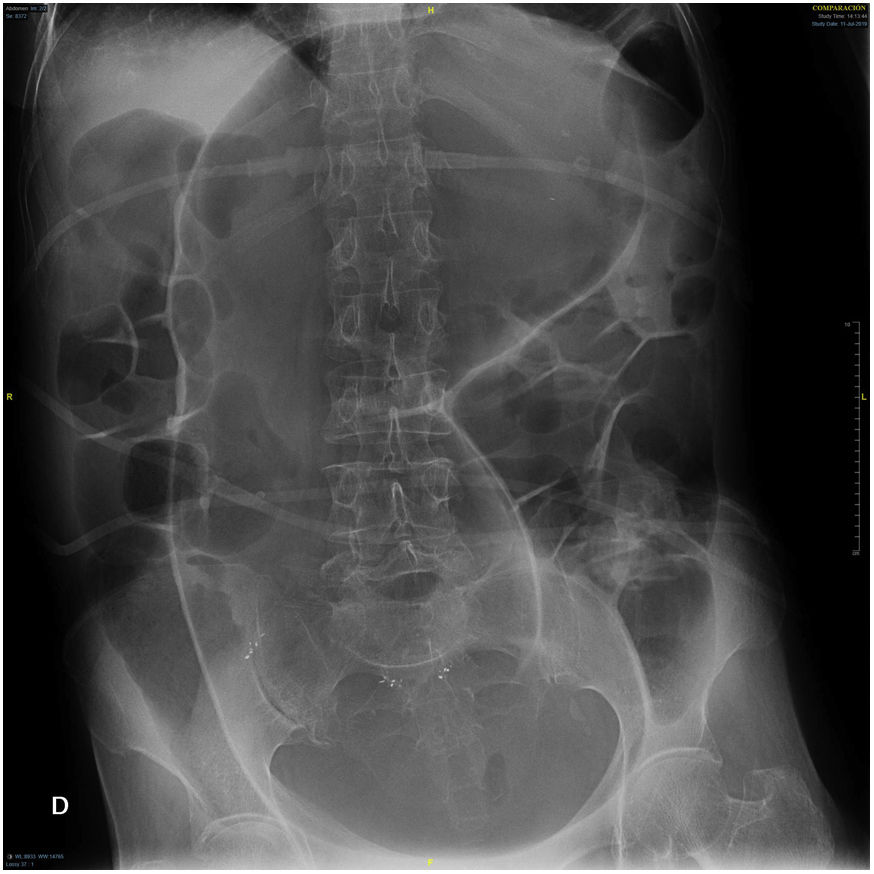

An abdominal X-ray was performed (Fig. 1), shown below. The objective findings allowed a diagnosis of certainty to be made.

Clinical course and diagnosisThe abdominal X-ray showed megacolon, without clear signs of intestinal obstruction.